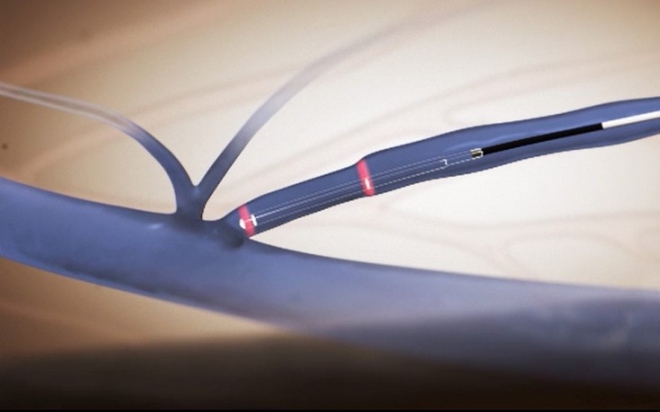

Ανώδυνη ενδοφλεβική θεραπεία των κιρσών με δακτυλίους laser

Τα σημαντικά πλεονεκτήματα των ενδοφλεβικών θεραπειών οδήγησαν στην ανάπτυξη αρκετών εναλλακτικών επιλογών (laser διαφόρων ειδών, ραδιοσυχνοτήτων, μηχανικών, χημικών σκευασμάτων, κ.τ.λ). Σήμερα, μια νέα γενιά ανώδυνων laser με ειδικούς ενδοφλεβικούς καθετήρες καθιστά την θεραπεία των κιρσών ακόμη πιο ανώδυνη, ασφαλή και σίγουρη έναντι κάθε άλλης διαθέσιμης τεχνικής όπως επίσης και έναντι των laser της προηγούμενης γενιάς.

Η νέα γενιά ανώδυνων laser με ειδικούς ενδοφλεβικούς καθετήρες διπλών δακτυλίων εκπομπής (laser double-ring 360ο) επιτυγχάνει την θεραπεία των κιρσών με τη εφαρμογή ελάχιστης, αλλά απόλυτα εστιασμένης, ενέργειας στα τοιχώματα του αγγείου. Η εστιασμένη δράση του laser συρρικνώνει ομοιόμορφα τα τοιχώματα και σφραγίζει οριστικά και με απόλυτη ασφάλεια την πάσχουσα φλέβα ελαχιστοποιώντας το ενδεχόμενο επιπλοκών (αιματωμάτων, μετεγχειρητικού πόνου, κ.α.).

Η θεραπεία μπορεί να πραγματοποιηθεί χωρίς νάρκωση και νοσηλεία, συχνά δεν απαιτεί καθόλου τομές και δεν αφήνει ουλές. Η κινητοποίηση του ασθενούς είναι άμεση και τα ποσοστά υποτροπών μικρότερα του 5%. Αποτελεί ιδανική επιλογή θεραπείας της μείζονος και της ελάσσονος σαφηνούς, ακόμη και σε ασθενείς με συνοδά προβλήματα (σε αντιπηκτική αγωγή, παχύσαρκους, διαβητικούς, κ.α.). Σήμερα, με την χρήση των πιο εξελιγμένων τεχνολογιών μπορούμε να προσφέρουμε στους ασθενείς αμεσότερη και ακριβέστερη διάγνωση, ανώδυνη και αποτελεσματική θεραπεία, απαλλάσσοντας από τα βασανιστικά συμπτώματα των φλεβικών παθήσεων.